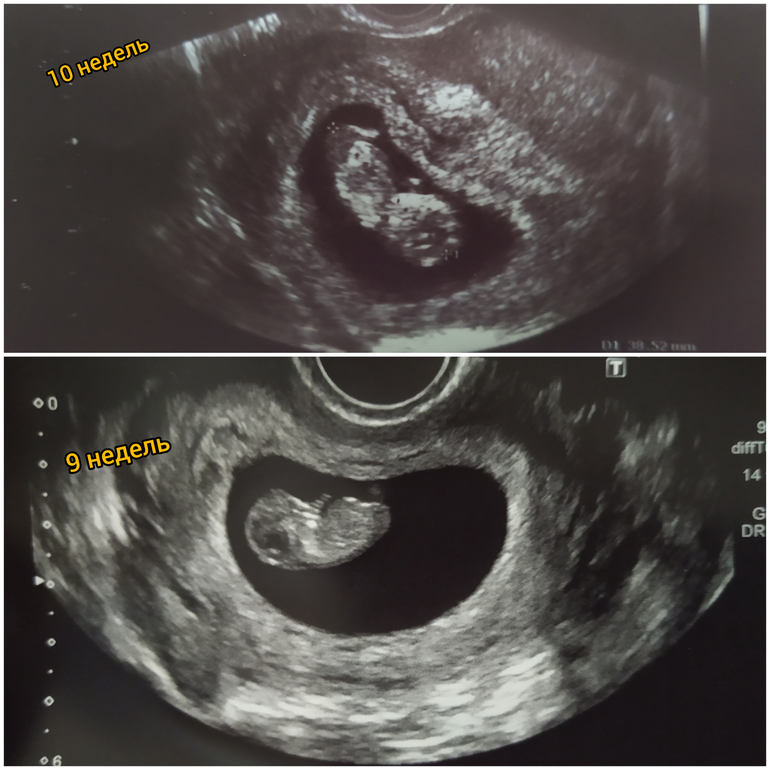

10 недель полных🐣🐣🐣